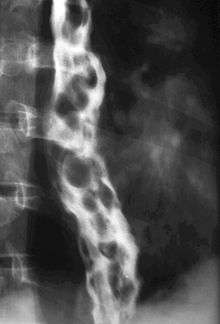

In medicine (gastroenterology), esophageal varices (or oesophageal varices) are extremely dilated sub-mucosal veins in the lower third[1] of the esophagus. They are most often a consequence of portal hypertension, commonly due to cirrhosis; patients with esophageal varices have a strong tendency to develop bleeding.

Dilated submucosal veins are the most prominent histologic feature of esophageal varices. The expansion of the submucosa leads to elevation of the mucosa above the surrounding tissue, which is apparent during endoscopy and is a key diagnostic feature. Evidence of recent variceal hemorrhage includes necrosis and ulceration of the mucosa. Evidence of past variceal hemorrhage includes inflammation and venous thrombosis.